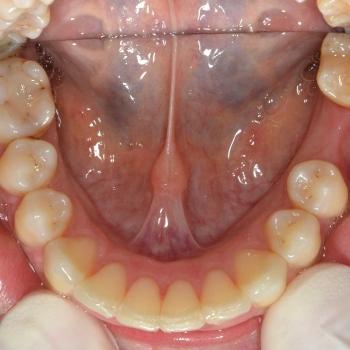

Tünde a felső fogív torlódása, illetve az alsó metszőfogak között található rések miatt keresett fel. Az első találkozásunk alkalmával azonban fény derült a középvonalak eltolódására, enyhe mélyharapásra, a felső metszőfogak túlzott elülső pozíciójára, illetve a régóta hiányzó alsó 6-os fog helyének beszűkülésére is, így a kezelési terv ezen problémák megoldására is kitért.

Tünde végül úgy döntött, hogy nem csak az esztétikai, de a funkciós problémák is szeretné megoldani, melyhez hagyományos fém fogszabályozót választott. A fogszabályozáshoz különböző kiegészítőket is igénybe vettünk úgy, mint harapásemelő, különböző intermaxillaris gumihúzások, illetve egy speciális szájpadi mini-implantátum a hozzá kapcsolódó transpalatinalis ívvel (hibrid transpalatinal ív), ami minimalizálta a hátsó fogak mozgását, miközben a felső metszőfogak hátrafele mozogtak.

A kezelés végére minden problémát sikerült megoldanunk, a középvonalak korrekcióját leszámítva. Ennek ellenére, mivel a felső középvonal az arc tengelyében helyezkedik el, az esztétikai eredmény nem csorbult és a funkciót sem befolyásolta. A jobb alsó 6-os fog implantációs pótlása a fogszabályozás befejeztével kezdődött meg.